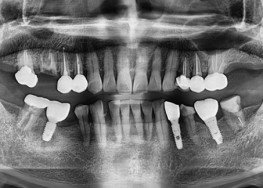

임플란트-치료-전후사진